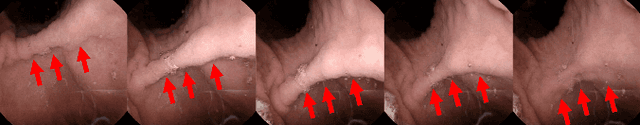

Abstract:Magnetically controlled capsule endoscope (MCCE) is an emerging tool for the diagnosis of gastric diseases with the advantages of comfort, safety, and no anesthesia. In this paper, we develop algorithms to detect and measure human gastric peristalsis (contraction wave) using video sequences acquired by MCCE. We develop a spatial-temporal deep learning algorithm to detect gastric contraction waves and measure human gastric peristalsis periods. The quality of MCCE video sequences is prone to camera motion. We design a camera motion detector (CMD) to process the MCCE video sequences, mitigating the camera movement during MCCE examination. To the best of our knowledge, we are the first to propose computer vision-based solutions to detect and measure human gastric peristalsis. Our methods have great potential in assisting the diagnosis of gastric diseases by evaluating gastric motility.